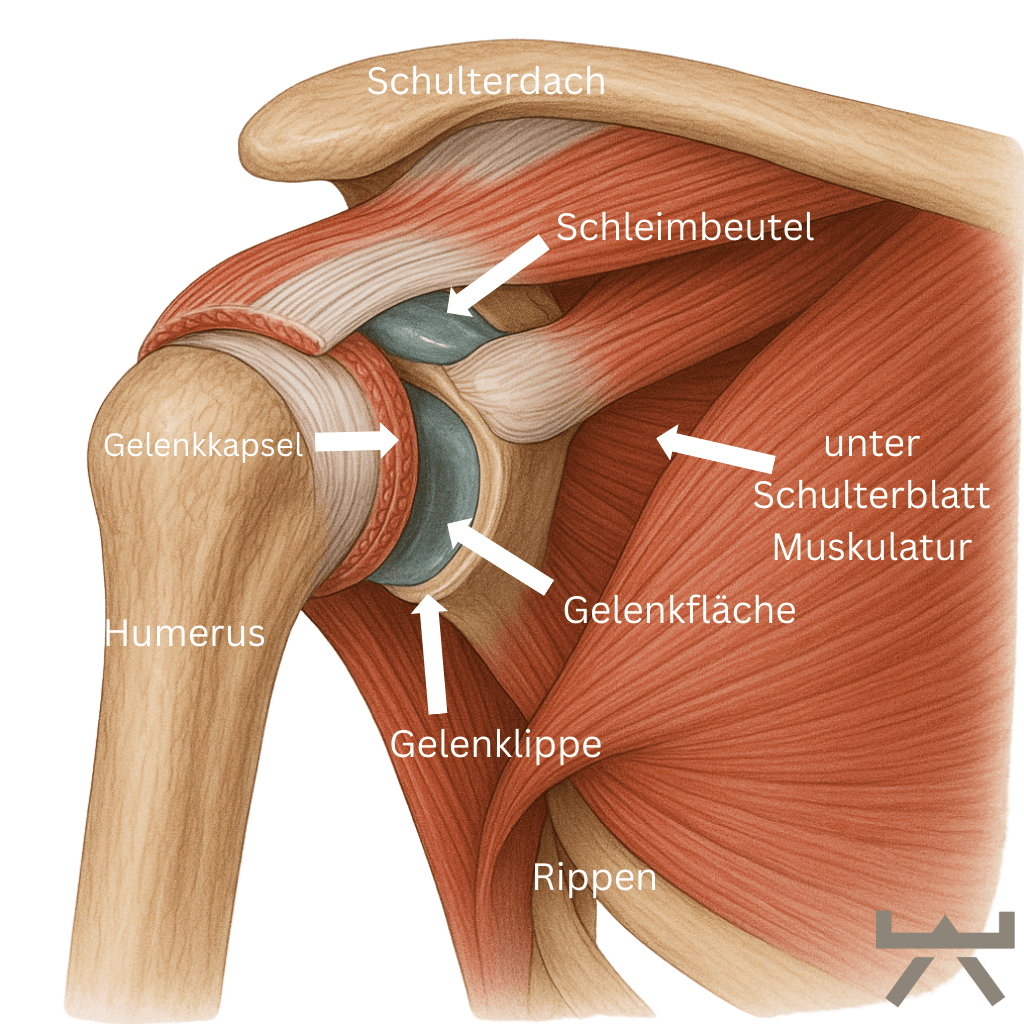

ANATOMIE

Die Schulter ist geschickt zusammengesetzt. Es ist ein Komplex aus nicht weniger als 4 Gelenken, nämlich:

- Das Glenohumeralgelenk. Dies ist die Verbindung zwischen Oberarm und Schulterblatt. Kopf und Pfanne sind durch die Schulterkapsel, auch Rotatorenmanschette genannt, verbunden. Kleine Muskeln, die extrem wichtig sind, um den Schulterkopf in der Pfanne zu halten.

- Das AC-Gelenk. Dies ist die Verbindung zwischen dem Schulterdach (Acromion auf Latein) und Schlüsselbein (Clavicula auf Latein).

- Das SC-Gelenk. Dies ist die Verbindung zwischen dem Brustbein (Sternum auf Latein) und Schlüsselbein (Clavicula auf Latein).

- Das scapulathorakale Gelenk. Dies ist die Verbindung des Schulterblatts (Scapula) zum Brustkorb (Thorax). Das Schulterblatt ist durch Muskeln am oberen Rücken befestigt.

Verglichen mit der tiefen knöchernen Hüftpfanne ist die Schulterpfanne eher als kleine Schale zu bezeichnen. Diese Schale wird durch das Labrum noch verstärkt. Das Labrum ist einen Knorpelring, der direkt an der Gelenkpfanne der Schulter ansetzt. Das Labrum ist wiederum mit den Muskeln der Rotatorenmanschette verbunden, die zusammen die Schulterkapsel bilden. Sie sollten diese Muskeln als eine dynamische Gelenkpfanne betrachten, die zur Stabilisierung des Schulterkopfes beiträgt, indem sie genau im richtigen Moment angespannt wird, wenn sie ihre Bewegungen ausführen.

Für die Anforderungen, die wir an die Schulter stellen, ist ihre Anatomie sehr sinnvoll. Die minimale Gelenkpfanne ermöglicht es uns, den Arm frei in allen Richtungen zu bewegen. Durch diese Bewegungsfreiheit wird die Stabilisierung der Schulter für den Körper jedoch schwieriger.